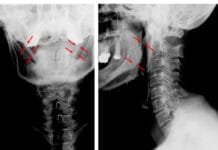

Prosthetics ─ More missing teeth are associated with epileptic patients due to decay, periodontal disease, or injury. We know that replacing teeth gives patients a better quality of life, but prosthetics may be more complicated.

Epileptic patients who suffer from tonic-clonic seizures (grand mal) with involuntary muscle contractions that include the masticatory system require special treatment. It is the usual recommendation to have fixed prosthesis instead of removable.12 Dentures and partials can break or create choking hazards during any seizure, and it should be considered when at all possible to create fixed prosthetic solution.